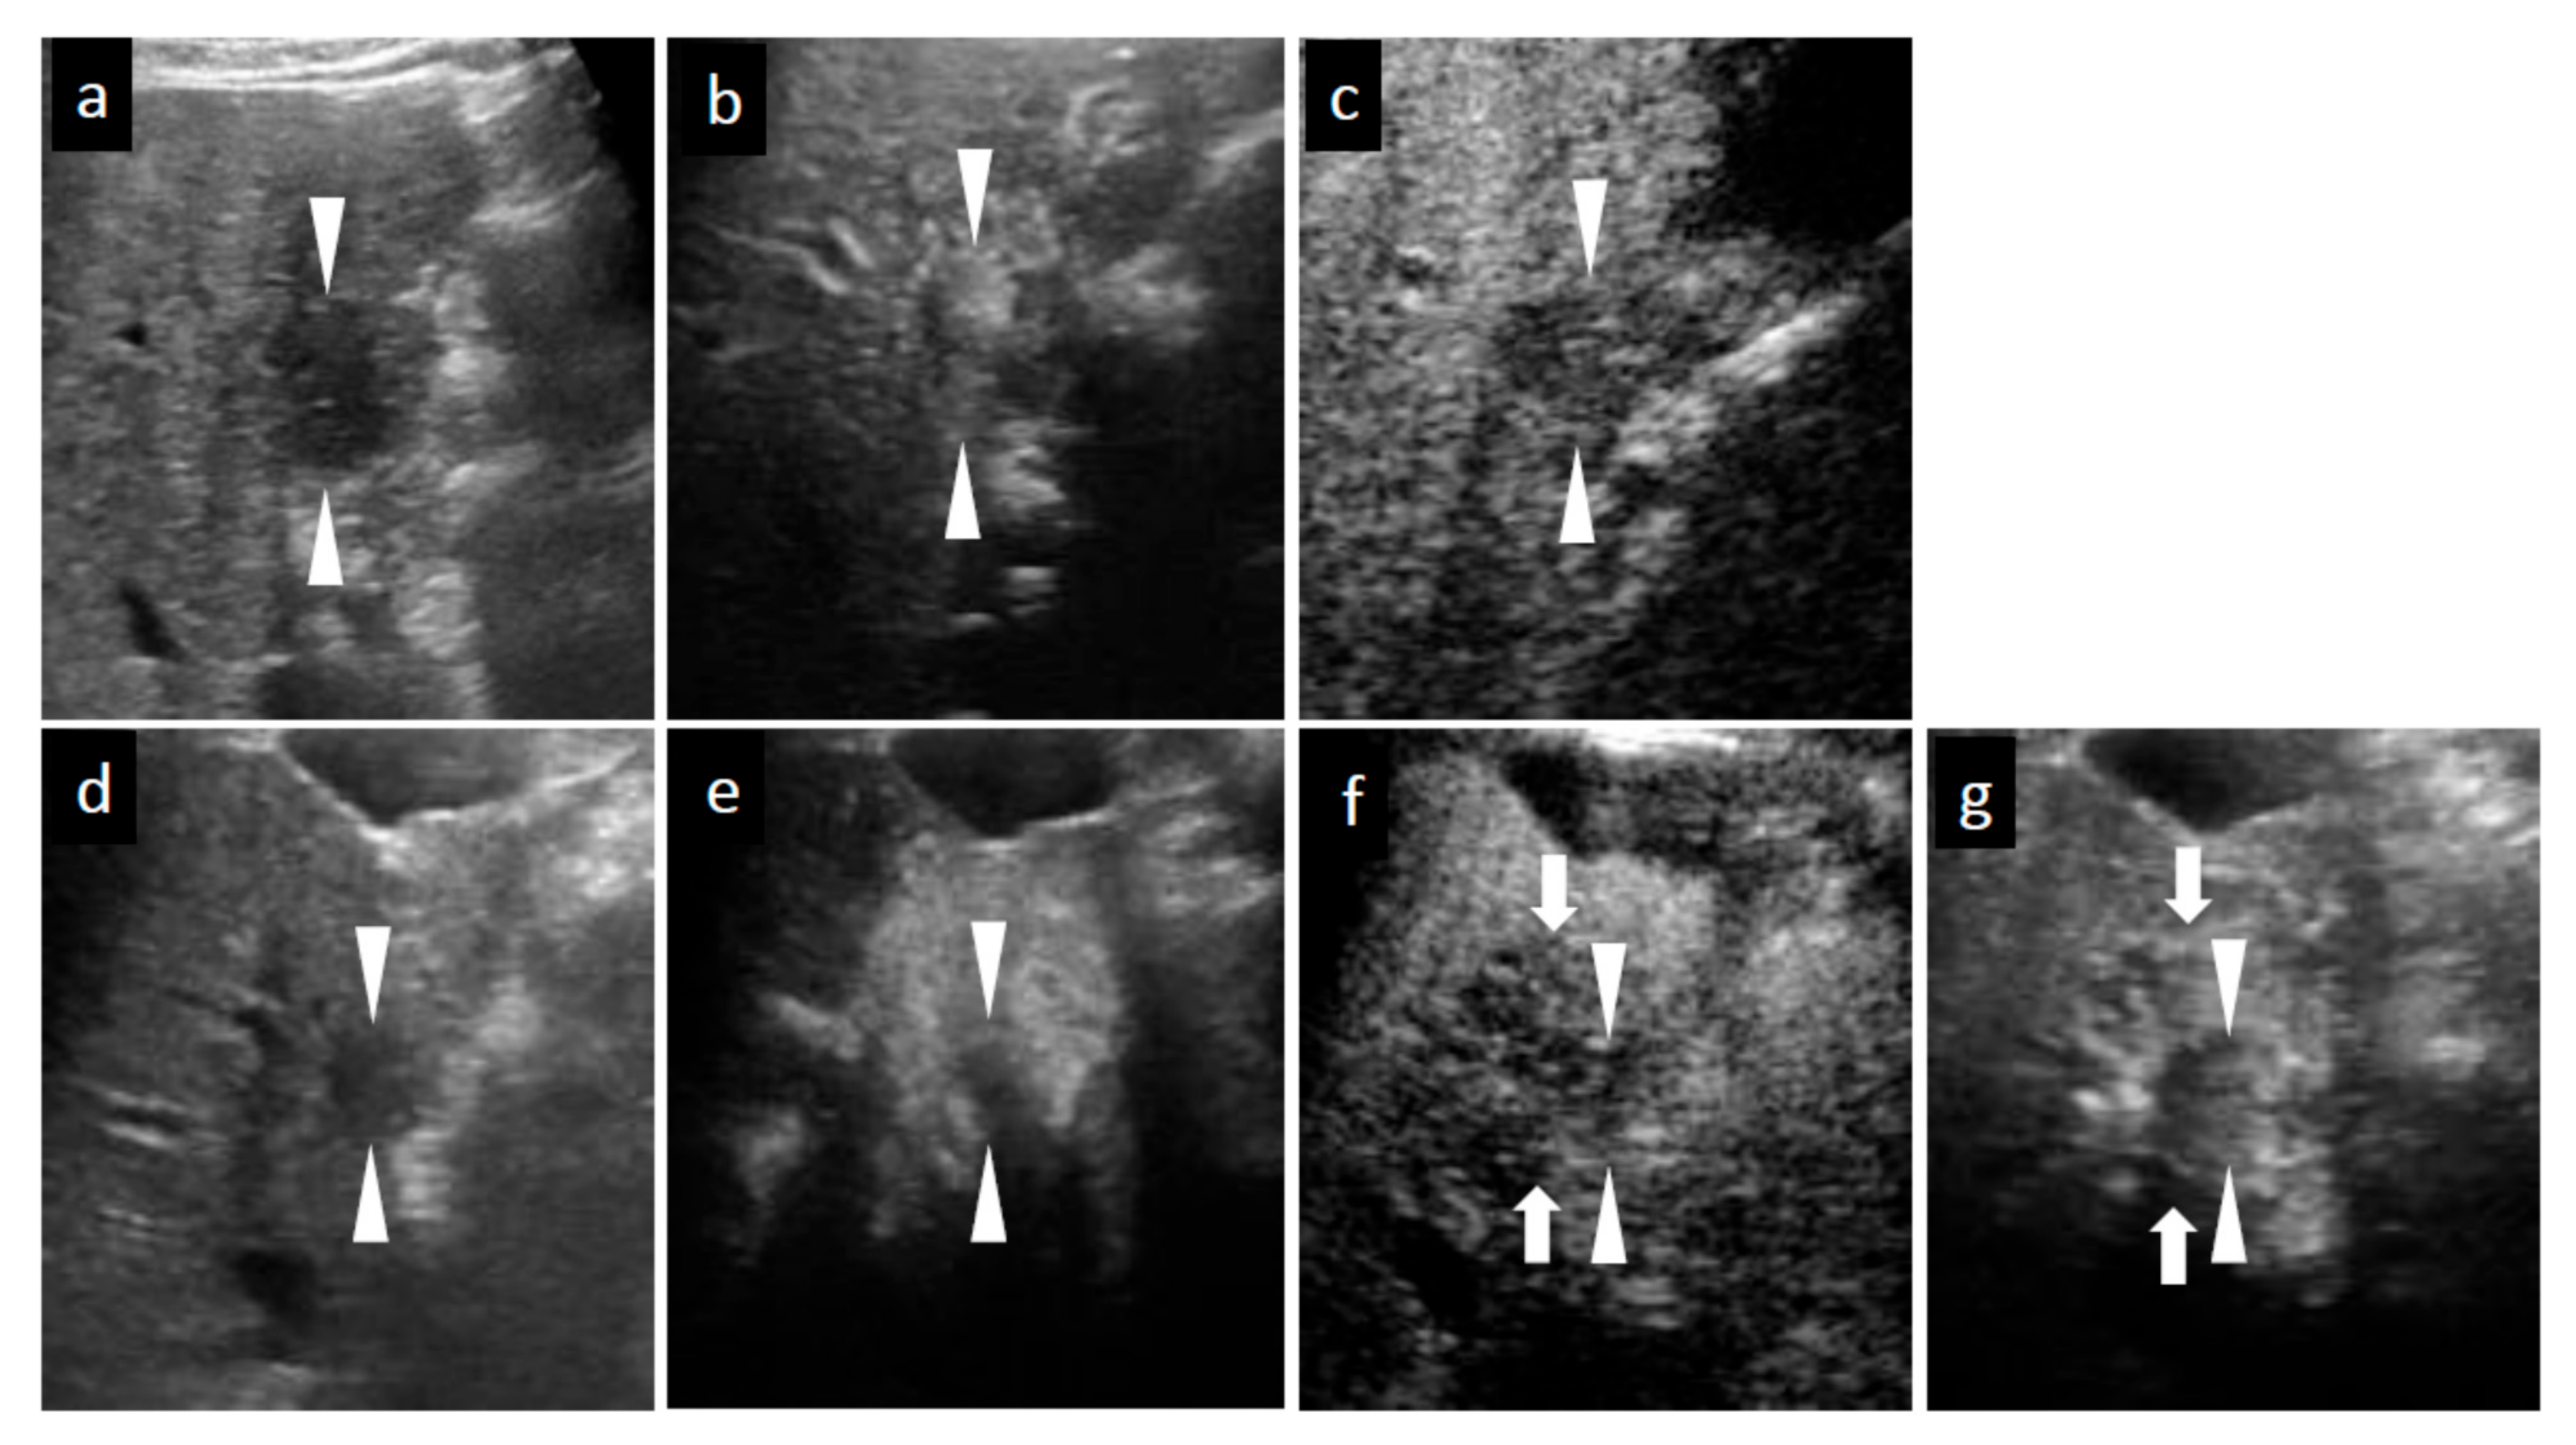

Figure 2.

Grayscale ultrasound (US), contrast-enhanced US with Sonazoid (SCEUS), and contrast-enhanced MRI (CEMRI) images before and seven months after radiotherapy (RT) for a HCC lesion (maximum diameter: 22 mm) in segment IV, evaluated as no local recurrence after RT. A safe punctuation was difficult, as the lesion was located behind the gallbladder. The patient refused surgical resection, so they received RT. SCEUS before RT (a–c): A hypoechoic lesion was observed using grayscale US (a). This lesion showed hypervascularity during the arterial phase (AP) of SCEUS (b) and hypoechoic (perfusion defect) during the post vascular phase (PVP) (c). SCEUS seven months after RT (d–g): Grayscale US showed a hypoechoic nodule and a reduction in tumor size (d). AP SCEUS showed a disappearance of vascularity of the HCC lesion and hypervascularity of the surrounding liver parenchyma (e). Both the HCC lesion and the surrounding liver parenchyma appeared as a perfusion defect during the PVP (f). After re-injection of Sonazoid during the PVP, the HCC showed hypovascularity and the surrounding liver parenchyma showed hypervascularity (g). AP CEMRI before (h) and seven months (i) after RT: Before RT, this lesion showed hyperintensity during AP CEMRI (h). Both the HCC lesion and the surrounding liver parenchyma appeared as hyperintensity at seven months after RT (i). Seven months after RT, we observed a discrepancy between the vascularity shown by SCEUS and that by CEMRI, but the lesion has not recurred for more than 3 years, suggesting that the SCEUS findings might be correct. Arrowheads show the margins of the HCC lesion. Arrows show the margins of irradiated surrounding liver parenchyma.